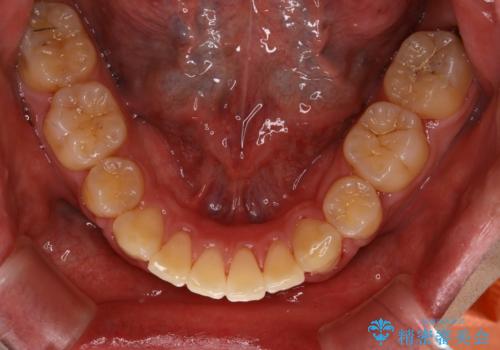

- 上顎前歯の突出感と下顎前歯のガタつきが主訴で来院されました。

出っ歯とガタつきの改善を行うには抜歯が必要と診断し、上下左右第一小臼歯を抜歯する計画を立てました。

ワイヤー治療では歯の傾きを抑えながら大きい距離の移動が可能で、かみ合わせが深くなるリスクも少ないです。

- 矯正治療後の保定が不十分だと後戻り(元の位置に戻ろうとする動き)をします